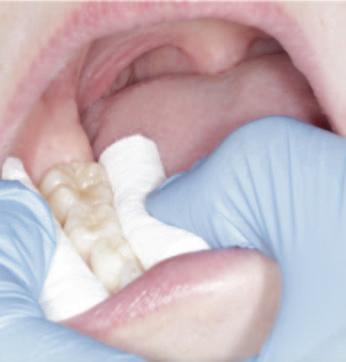

Process of fissure sealing with high-viscosity glass ionomer using the atraumatic restorative treatment technique3

1. Employ a four-handed technique where possible.

2. Achieve isolation using cotton wool rolls (Figure 2).

3. Dislodge plaque and debris with a probe and clean the surfaces using wet cotton pellets or a toothbrush.

4. Apply an enamel conditioner (e.g., 20% polyacrylic acid such as GC Cavity Conditioner) for 10 seconds (Figure 3).

5. Remove the conditioner and dry the surface, using wet, and then dry, cotton pellets. Care should be taken not to desiccate the enamel.

6. Apply a high-viscosity GI material, such as GC Fuji IX, directly onto the tooth using an applicator gun, dental instrument, or a gloved finger lubricated with petroleum jelly (Figure 4a).

7. Manipulate the material into the pits and fissures using finger pressure (Figure 4b).

8. Remove finger in a lateral direction after 10-15 seconds.

9. Remove excess with an instrument such as an excavator, and adjust occlusion as required.

10. Place a new layer of petroleum jelly and allow the material to set fully while maintaining isolation (Figure 5).

FIGURE 1: Hypomineralised mandibular right first permanent molar with early post-eruptive breakdown – suitable for a GI sealant. Natasha Lemasney BA BDentSc MFD RCSI MSc Senior House Officer, Paediatric Dentistry Cork University Dental School and Hospital Siobhán Lucey BDS NUI MFDS